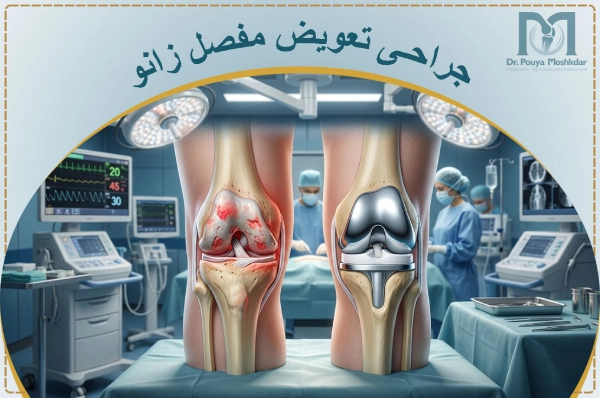

عمل تعویض مفصل زانو (Knee replacement) یک جراحی ارتوپدی پیشرفته است که در آن بخش های آسیب دیده یا فرسوده مفصل زانو با قطعات مصنوعی جایگزین میشوند. این عمل برای بیمارانی انجام میشود که دچار آرتروز شدید، آسیب دیدگی یا بیماری های مفصلی هستند و درد یا محدودیت حرکتی آن ها با روشهای غیرجراحی مانند تزریق ژل هیالورونیک اسید به زانو بهبود نیافته است. مفصل مصنوعی، عملکرد طبیعی زانو را بازمیگرداند و فعالیت های راه رفتن و نشستن و … را بهبود میبخشد.

آرتروز: آرتروز یکی از شایع ترین دلایل عمل زانو است. در این حالت، غضروف های مفصل زانو که نقش محافظت از استخوان ها را دارند، به تدریج فرسوده و تحلیل میروند. این فرسایش باعث درد شدید، التهاب، سفتی و کاهش تحرک مفصل میشود.

پس از ورود به اتاق عمل، بیمار تحت بیهوشی قرار میگیرد و زانو با مواد ضدعفونی تمیز میشود. آنتیبیوتیک پیشگیرانه نیز تزریق میشود. بهترین جراح تعویض مفصل زانو با ایجاد یک برش در جلوی زانو، به مفصل دسترسی پیدا کرده و بافتهای نرم و عضلات را کنار میزند.

غضروف و استخوانهای آسیبدیده برداشته شده و سطح استخوانها با دقت شکلدهی میشود تا پروتز بهخوبی جایگذاری شود. پروتز شامل قطعات فلزی برای استخوان و قطعه پلاستیکی برای ایجاد سطح لغزنده است که بهطور محکم در جای خود نصب میشود.

پس از اطمینان از عملکرد صحیح پروتز، محل جراحی با بخیه بسته میشود و بیمار به اتاق ریکاوری منتقل میشود. برای اطلاعات بیشتر درباره جزئیات، مقاله مراحل جراحی تعویض مفصل زانو را بخوانید.